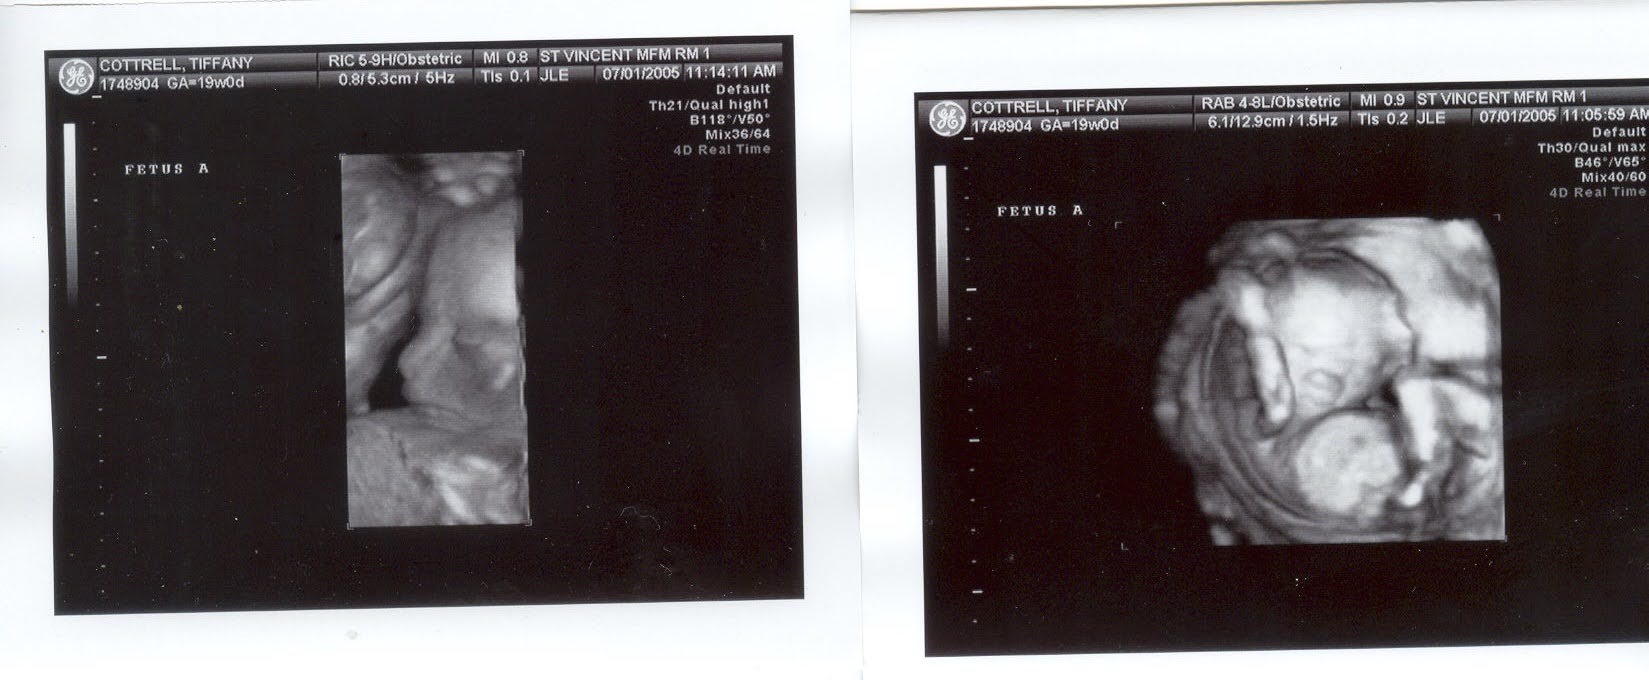

We talked about baby names and she sent me ultrasound photos. I could feel her excitement. This period of her life, as she waited for her baby girls to arrive, is where I have the most emails from her.

July 17, 2005 – Here are just two of the ultrasound pictures that I have. These are 3D. You can really see their faces. The doctors say they are two baby girls.